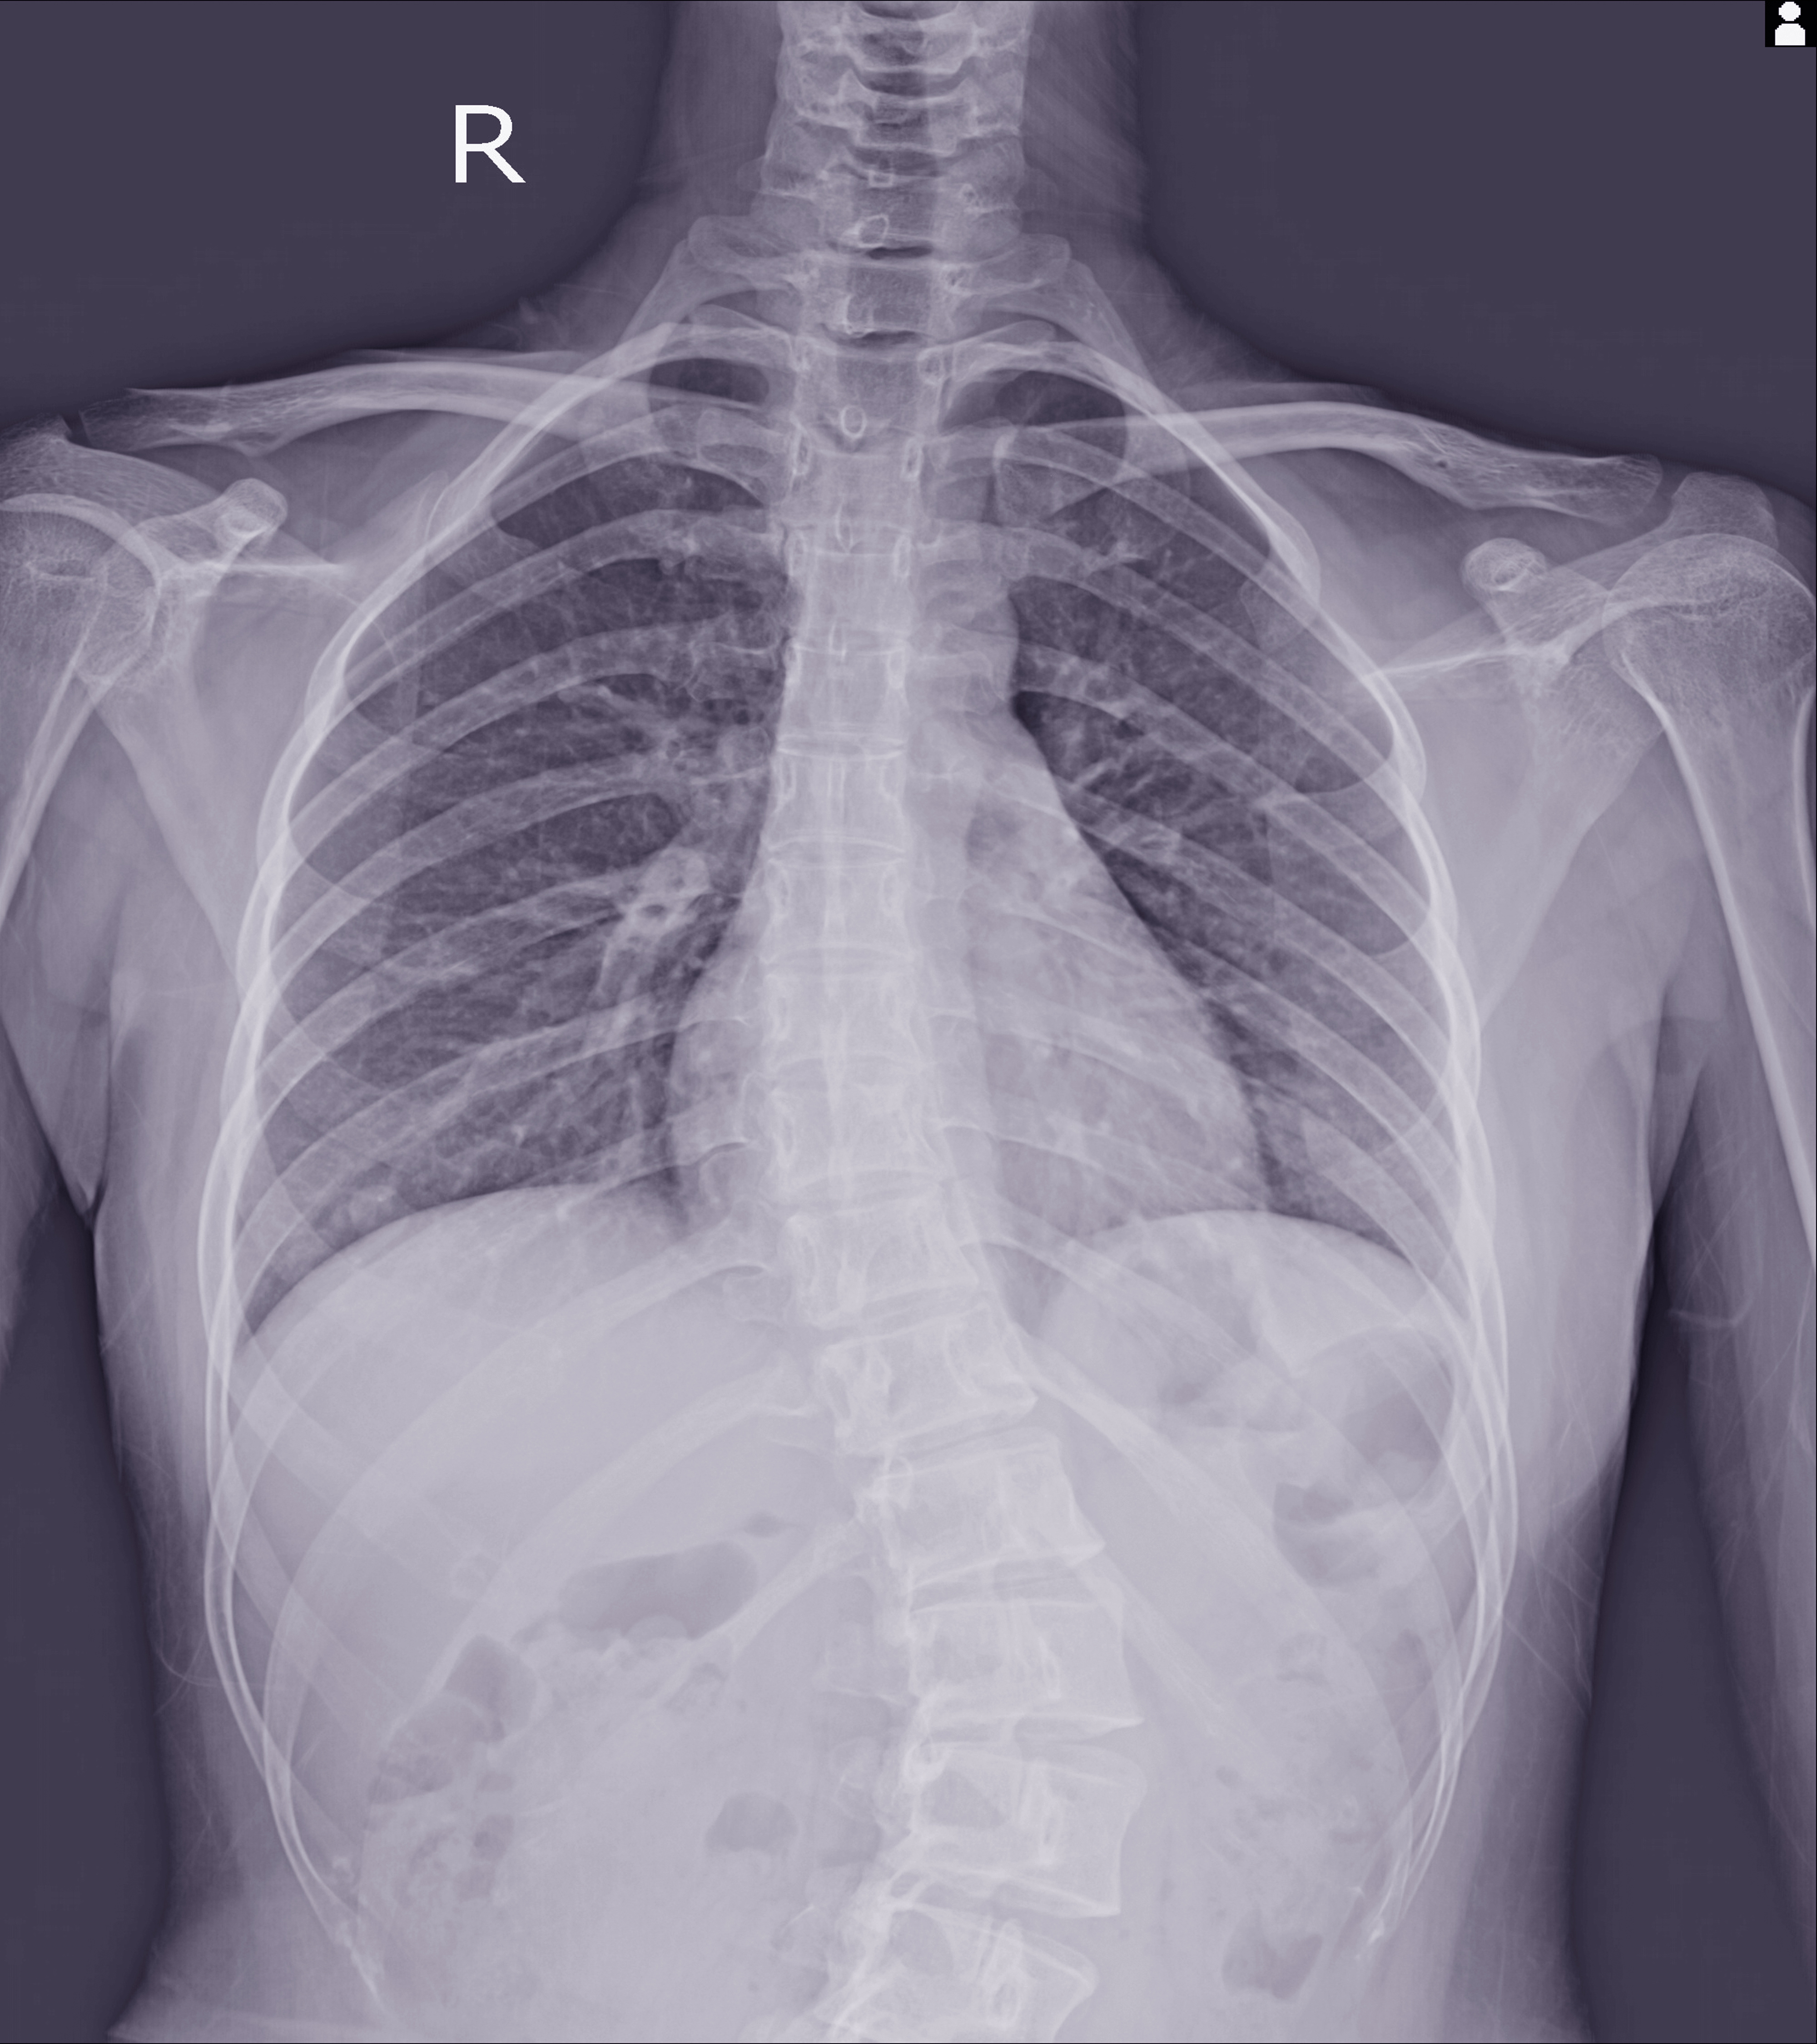

Radiografias da coluna inteira, que ajudam a determinar o ângulo e a gravidade da curvatura, conhecido como ângulo de Cobb.

A escoliose é uma deformidade da coluna vertebral que resulta numa curvatura lateral anormal, que pode aparecer em forma de "S" ou "C". Esta condição é mais comum durante o pico de crescimento antes da puberdade, mas pode afetar adultos também, devido ao desgaste da coluna ou a condições neuromusculares.